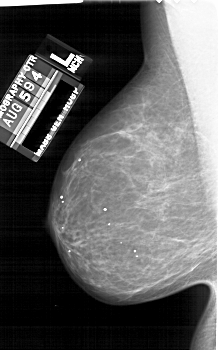

A_1689_1.LEFT_MLO

LEFT_MLO LINES 5941 PIXELS_PER_LINE 3706 BITS_PER_PIXEL 12 RESOLUTION 43.5 NON_OVERLAY